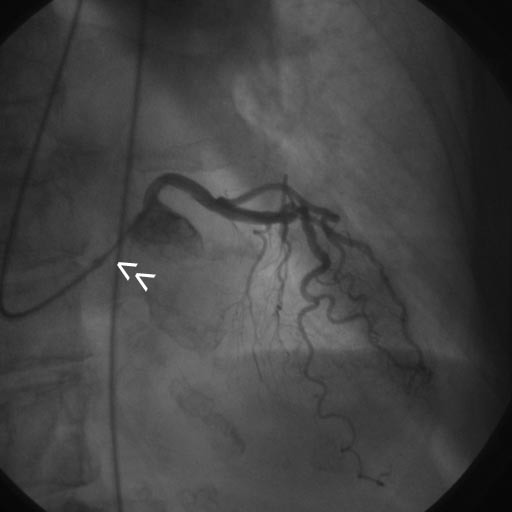

From www.giejournal.org

Doublecatheter method to prevent dislodgement during percutaneous transhepatic cholangioscopy What Is A Double Catheterization two radiopaque markers are positioned to identify the exit ports of both lumens. — cardiologists use a procedure called cardiac catheterization to see how well your heart is working. — cardiac catheterization is an imaging test that allows healthcare professionals to view a person’s blood. — cardiac catheterization (also called cardiac cath or coronary angiogram) is. What Is A Double Catheterization.